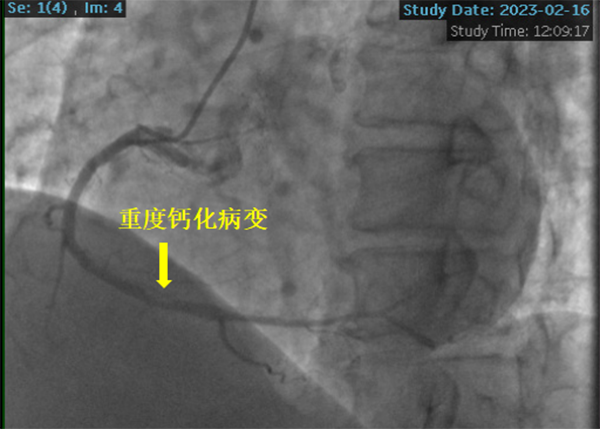

患者冠脈造影提示右冠狀動脈重度鈣化病變,狹窄程度達到90%-95%,左主干及左前降支彌漫鈣化伴中重度狹窄。潘德鋒主任團隊與心臟大血管外科王國祥主任團隊會診討論后,與患者家屬充分溝通病情,考慮到患者急性心梗、腦病等因素,決定采用冠脈支架植入術(shù)治療罪犯病變-右冠狀動脈重度鈣化病變。

冠脈鈣化病變被稱為“最硬的骨頭”或“最堅硬的堡壘”, 可導致介入器械難以通過或不能通過病變,即刻成功率低,并發(fā)癥發(fā)生率高等嚴重后果。針對患者病情及冠脈病變的復雜性,潘德鋒主任決定采用被譽為“拆彈專家”的沖擊波球囊技術(shù)治療冠脈嚴重鈣化病變。

2023年2月16日,在副院長楊煜的統(tǒng)籌指導下,心內(nèi)科冠脈專業(yè)專家組夏勇主任、徐通達主任、錢文浩主任、徐晤主任、陸遠主任等針對病例進行了充分的討論及術(shù)前準備,由潘德鋒主任進行手術(shù)操作。術(shù)中首先利用血管內(nèi)超聲明確患者冠狀動脈的鈣化情況及血管直徑,在血管內(nèi)超聲的指導下,選擇了4.0mm×12mm的沖擊波球囊,順利送入沖擊波球囊至鈣化病變部位,釋放脈沖,每次釋放10個脈沖,最終通過釋放80個脈沖,將鈣化斑塊進行了充分預處理,成功為患者植入了一枚冠脈支架,術(shù)后血管內(nèi)超聲顯示支架貼壁良好,患者癥狀明顯緩解,2月18日康復出院。